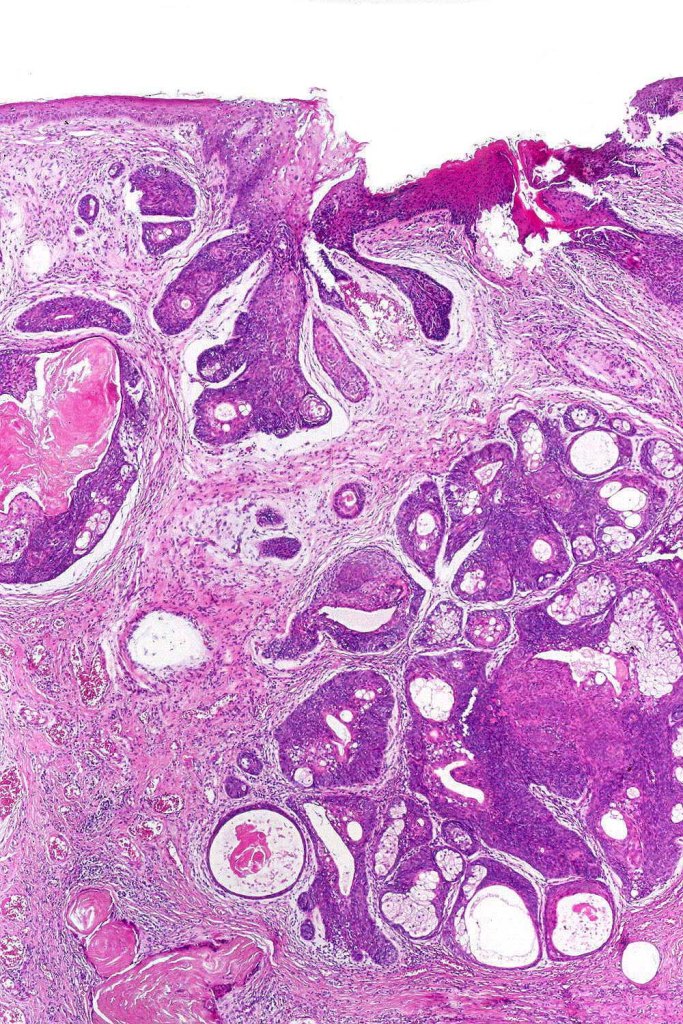

Histological features

•Variable origin from epidermis

•Typically multilobulated, occasioanlly cystic

•Collagenous pseudocapsule

•At the periphery, single or multiple germinative cell layers maturing into typical sebaceous cells (>50%)

•Variable peripheral palisading

•+/- basal mitoses (particularly in the so-called giant variant which should not be misdiagnosed as sebaceous carcinoma)